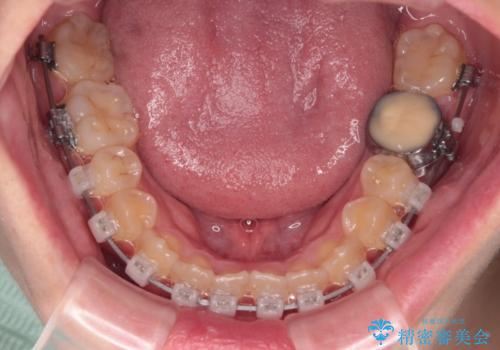

- クリアブラケット

上顎歯列が狭窄していたため、急速拡大装置により上顎骨を側方に拡大しながら、ワイヤー装置にて矯正治療を行うこととしました。

上顎骨を拡大することで、八重歯やデコボコを歯列に収めることができ、下顎の歯が外に位置していた奥歯の咬み合わせも改善することができました。

スペースも短期間に獲得できるため、1年程度で治療を終えることができました。